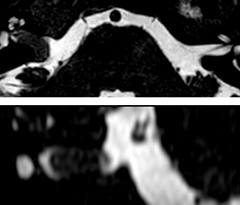

The 3D TSE T1w black blood MSDE sequence with fat suppression has an isotropic 0.8 mm voxel size and sagittal oblique and axial reformats are made. The images show superficial temporal artery thickening and peri-arterial fat infiltration. The 3D TSE PDw black blood MSDE with fat suppression has 0.55 mm isotropic voxels. The images shows focal involvement of the frontal branch of the superficial temporal artery.